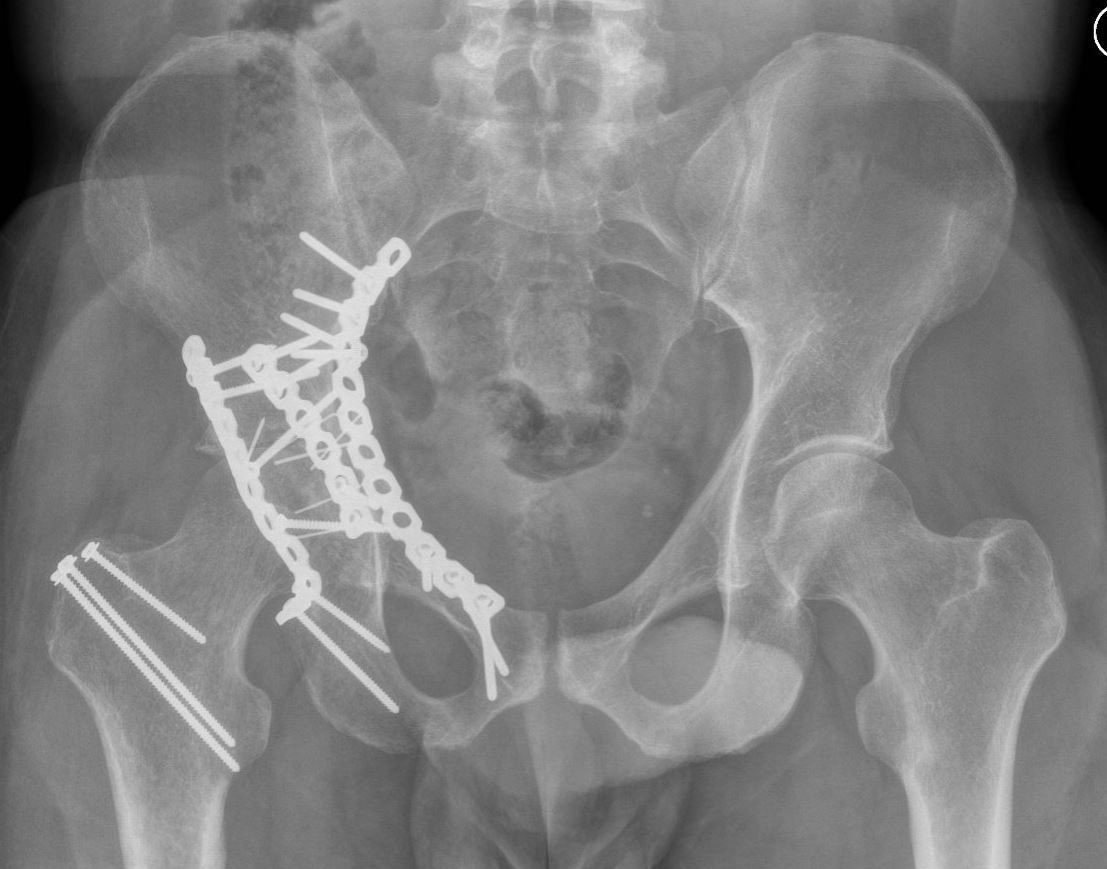

Indien de bekkenring op meerdere plaatsen gebroken is en het bekken daardoor instabiel is, dan zal uw traumachirurg meestal de ring op de gebroken plaatsen willen stabiliseren. Indien het bekken ernstig instabiel is en de bloeddruk daardoor ook verlaagd is, kan uw traumachirurg besluiten dat het bekken met spoed tijdelijk gefixeerd moet worden met een fixatie aan de buitenkant (een ‘fixateur externe’). In later stadium kan uw chirurg er voor kiezen deze fixateur toch langer te laten zitten, of de uitwendige fixatie te vervangen voor inwendige fixatie met platen en schroeven.

Als uw traumchirurg kiest voor inwendige fixatie, dan wordt het bekken meestal via een snee aan de voorkant van binnenuit (vanuit de buikzijde) met platen en schroeven gestabiliseerd.

Indien er sprake is van een gebroken heupkom, dan is het afhankelijk waar de breuk precies zit, of dat van binnenuit gestabiliseerd moet worden af via de achterkant.

Voor stabilisatie van het heiligbeen aan de achterkant, kan uw traumachirurg kiezen voor een fixatie met alleen schroeven of eventueel met een plaat erbij. Dit hangt af van het soort breuk en de voorkeur van uw traumachirurg.